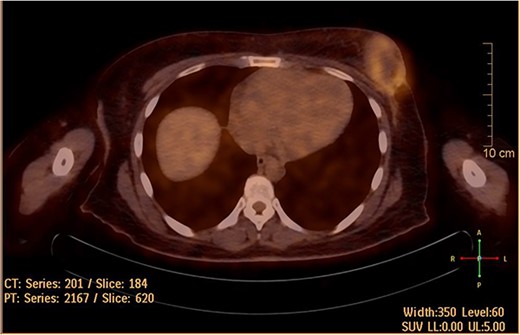

She underwent positron emission tomography/computed tomography after the sixth cycle, shown in Fig. 6. It showed a left breast hypermetabolic mass, compatible with known primary disease, there was no previous study for comparison, however, comparison with previous CT showed marked interval morphological regression of the tumor, no hypermetabolic lymph nodes, with no distant metastasis. Follow up breast ultrasound showed multifocal multicentric left breast lesions with few suspicious left axillary lymph nodes. The patient was seen in the surgical oncology outpatient clinic and prepared for mastectomy.

Hypermetabolic left breast mass in last positron emission tomography/computed tomography, following six cycles of IA.